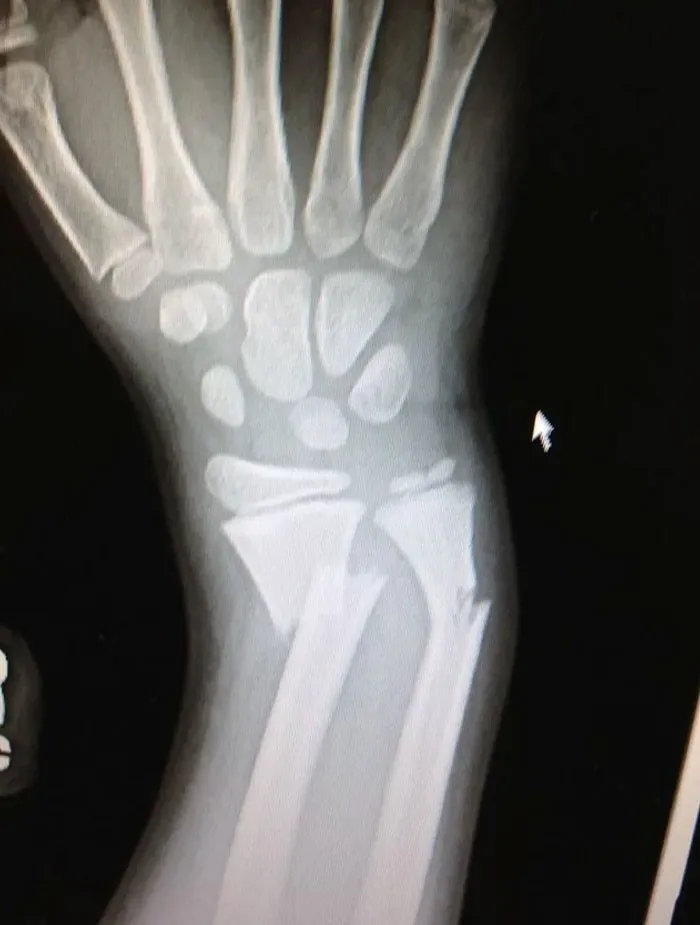

9. "Рентгенолог сказал, что перелома нет... Что-то я сомневаюсь"

24. "Рентгеновский снимок моего перелома руки в детстве"